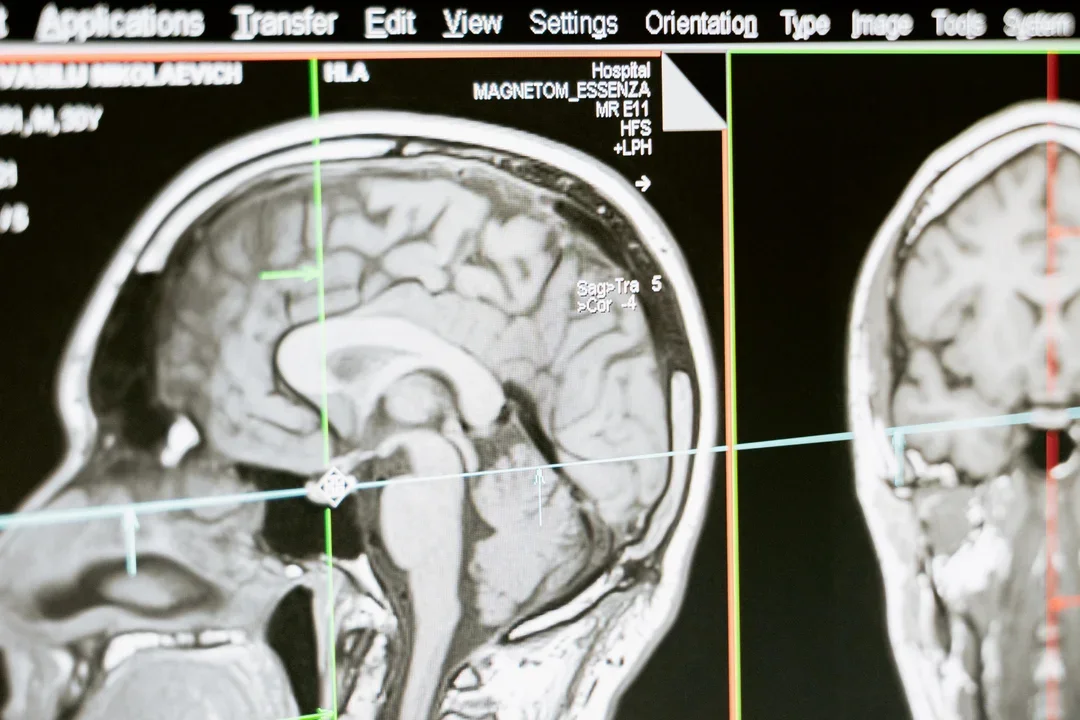

Średnio co 6,5 minuty ktoś w Polsce doznaje udaru mózgu. To pierwsza przyczyna trwałej niepełnosprawności wśród dorosłych Polaków. | foto pexels

Jak mówi nam dr Marta Bott-Olejnik, neurolog pracująca na co dzień na oddziale neurologicznym w szpitalu w Gryficach, w Polsce co 6,5 minuty doznaje ktoś udaru mózgu. Blisko 75 procent ataków to właśnie udary niedokrwienne. Ale młodzi ludzie myślą, że statystyki ich nie dotyczą. Tymczasem – choć dokładnych danych na razie brak – lekarze mówią głośno, że choroba dotyka coraz więcej osób jeszcze przed trzydziestką. Chorują nawet nastolatkowie. Szacuje się, że do roku 2030 udar mózgu będzie stanowić jeden z najpoważniejszych problemów medycznych.